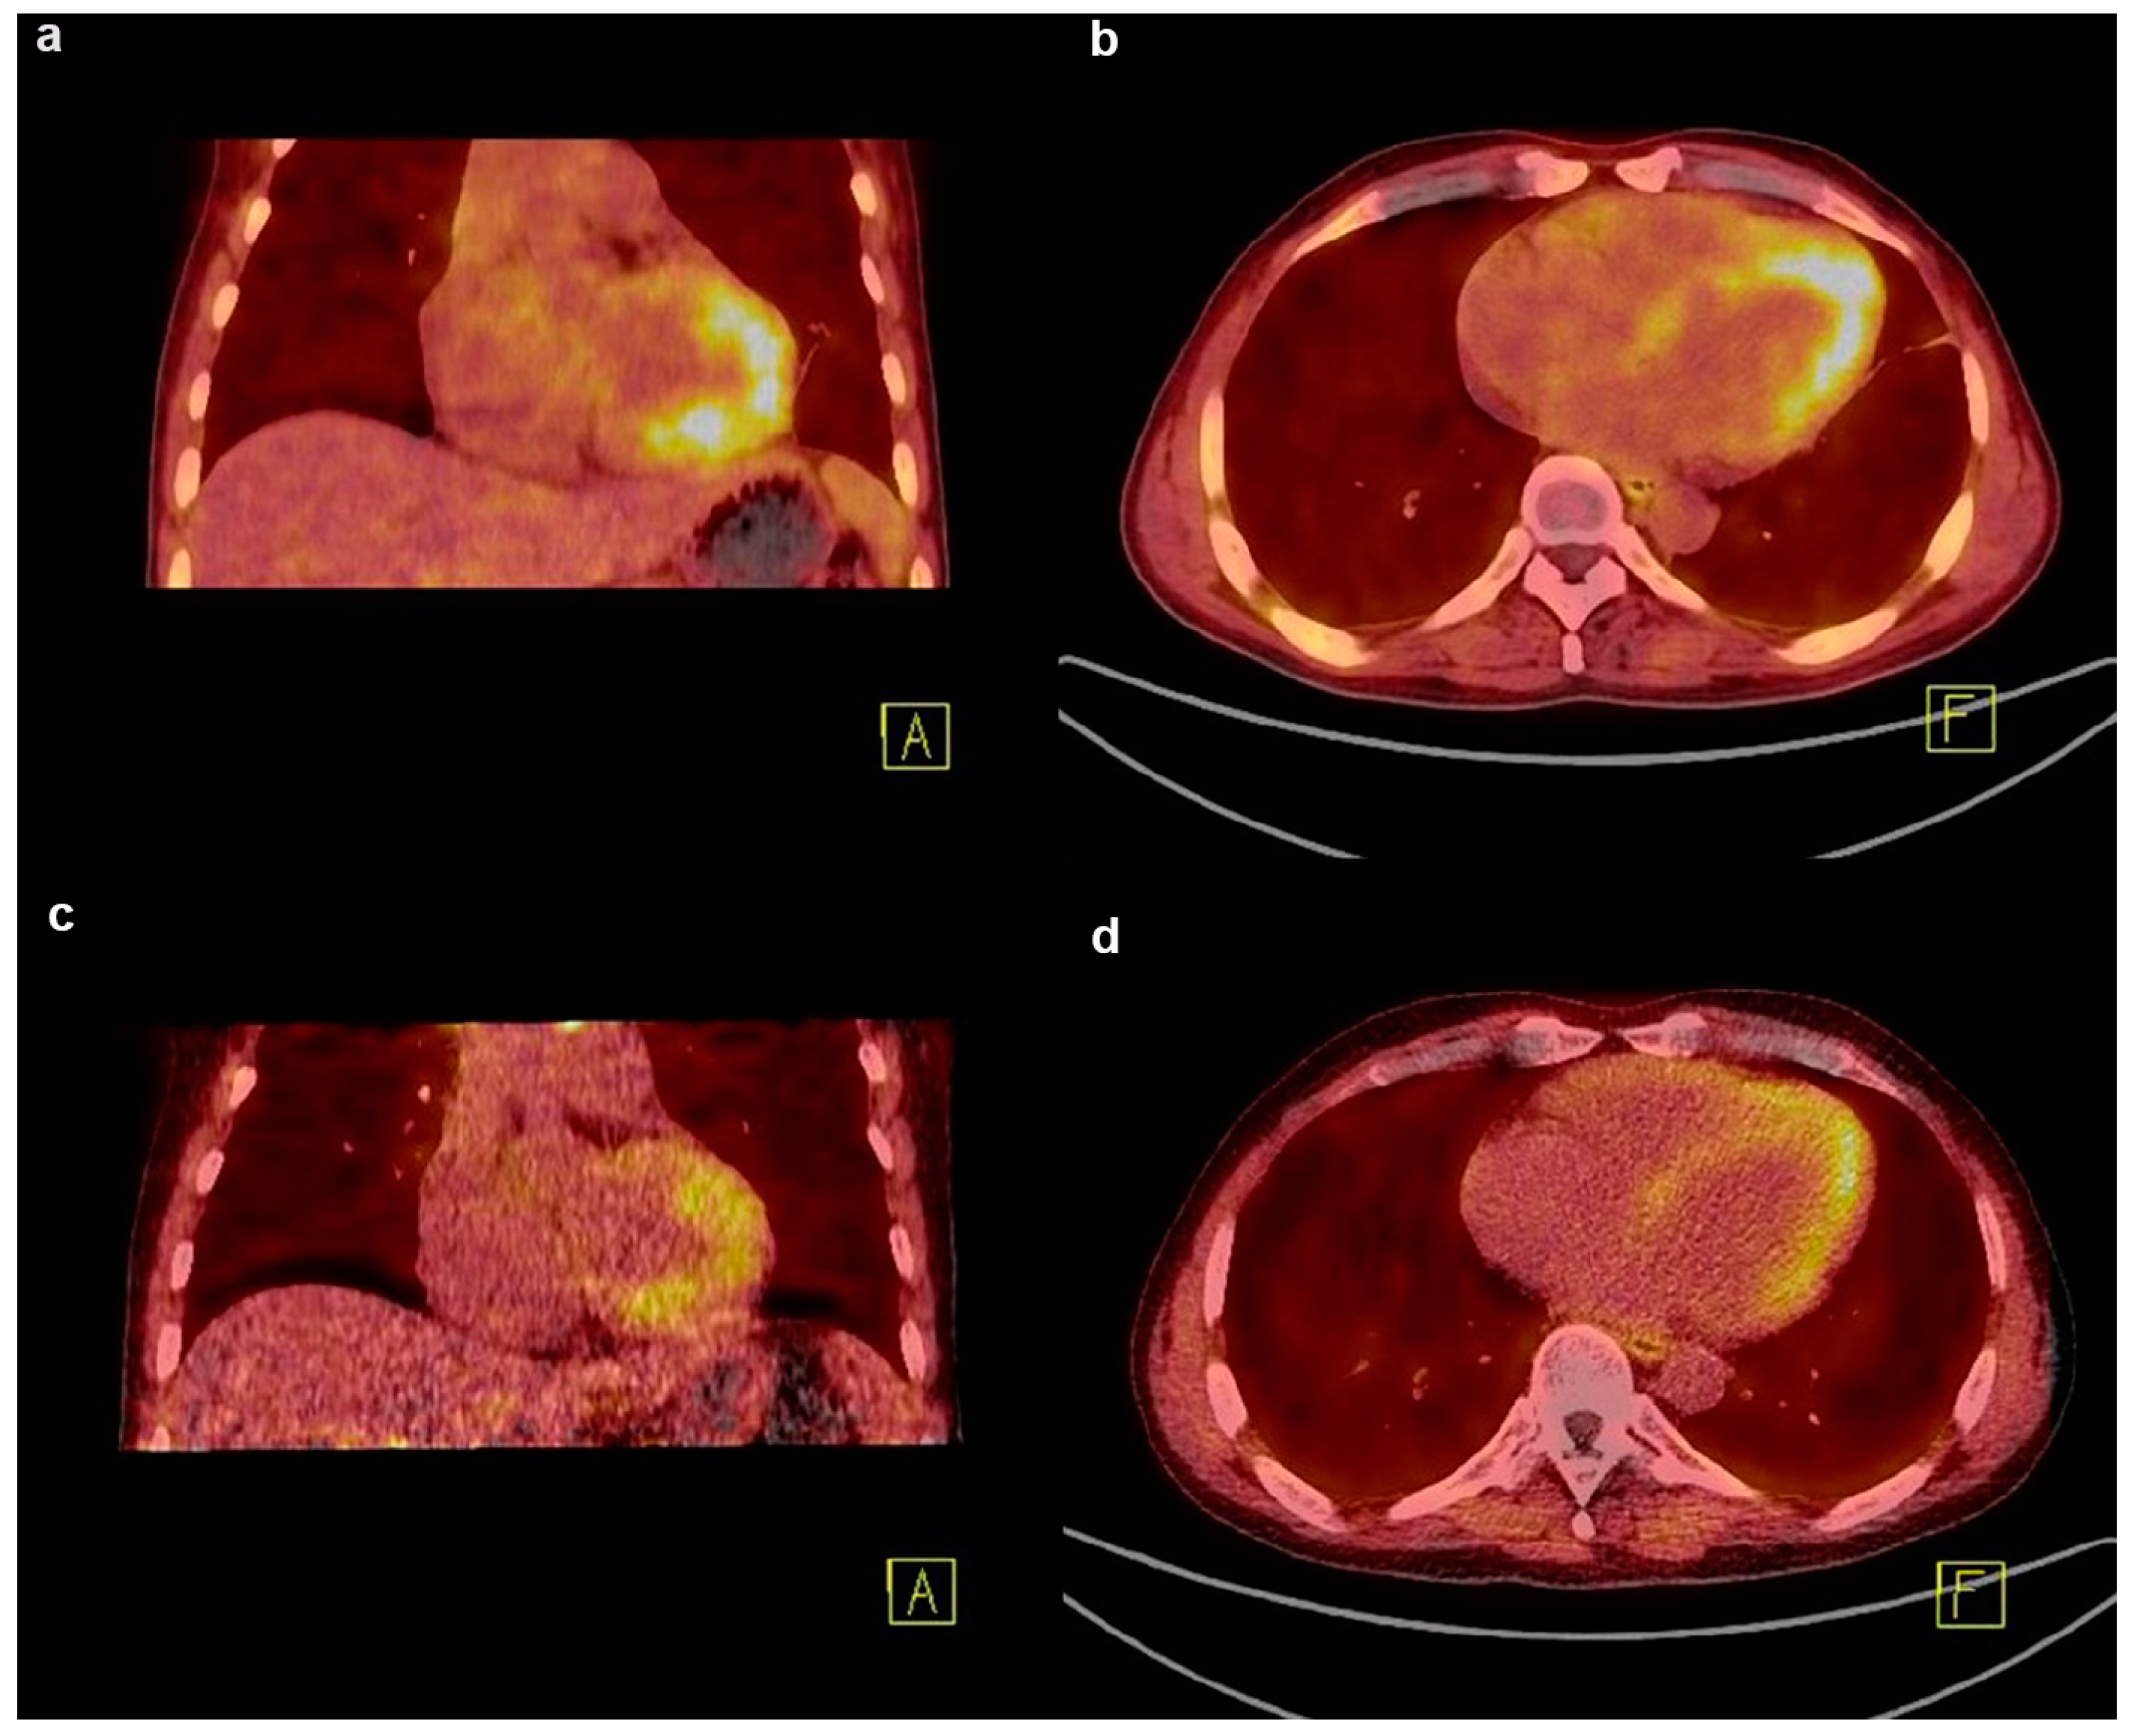

- Zhang, X.; Song, W.; Qin, C.; Lan, X. Different displays of 13N-NH3 myocardial perfusion and cardiac 68Ga-FAPI PET in immune checkpoint inhibitor-associated myocarditis-induced heart failure. Eur. J. Nucl. Med. Mol. Imaging 2023, 50, 964–965. [Google Scholar] [CrossRef]